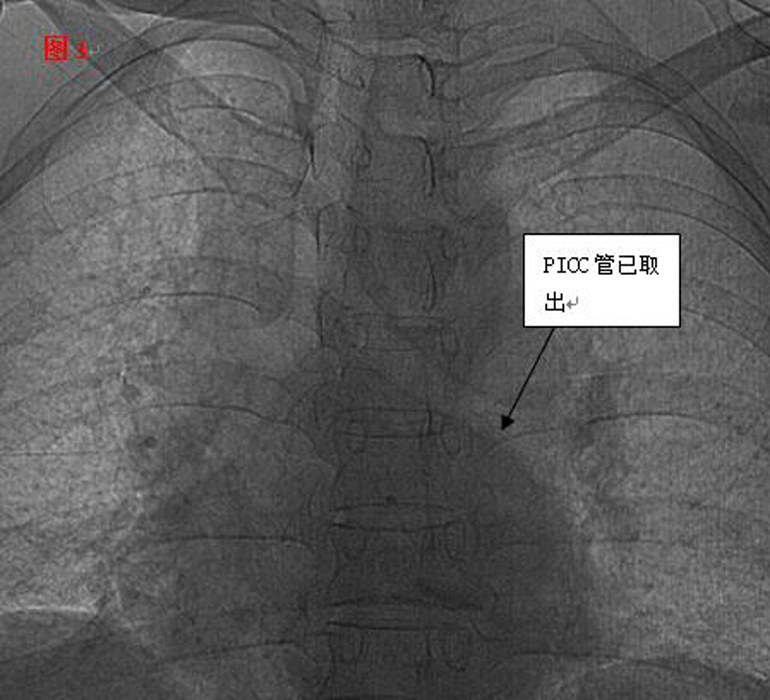

??? 手術(shù)遇到了艱巨的挑戰(zhàn),需更改手術(shù)方案。血管外科專家王李華教授及陸煒主任短暫商討后,臨時(shí)施妙招,先將PICC導(dǎo)管拉出心臟,再將圈套器牽引導(dǎo)管至下腔靜脈,捕捉后緩慢拉出體外,導(dǎo)管竟長(zhǎng)達(dá)30cm(見(jiàn)圖2)。

??? 憑借醫(yī)師的高超技術(shù)加上團(tuán)隊(duì)的密切合作,手術(shù)圓滿成功,30厘米的導(dǎo)管被完整取出,術(shù)后復(fù)查未見(jiàn)殘留。當(dāng)手術(shù)結(jié)束的那一刻,躺在手術(shù)臺(tái)上的麗琴由衷的感謝聲,以及在場(chǎng)觀摩學(xué)習(xí)人員的掌聲,讓手術(shù)室內(nèi)格外溫情。